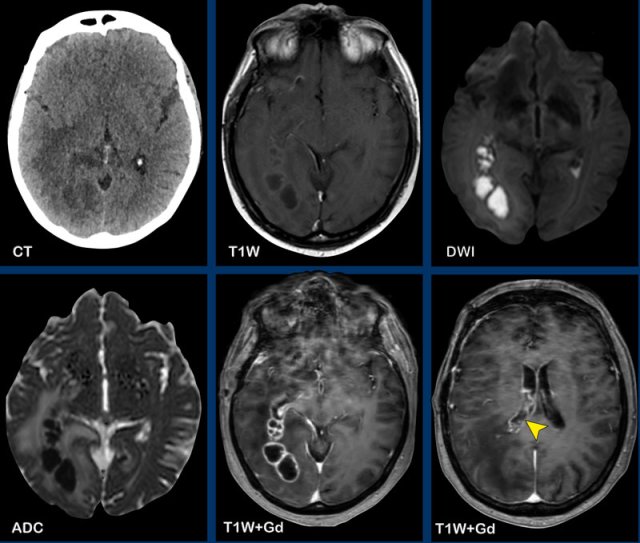

These images are of a 76-year old woman, who was confused after a fall.

First look at the images and then continue reading.

Question:

- What is the most likely diagnosis?

- Which findings are typical for this diagnosis?

The findings are:

- Hyperdense lesion on the NECT with some vasogenic edema.

- MR shows multiple lesions with solid enhancement and diffusion restriction.

- On T2W the lesions show a low signal intensity

- One lesion is located in the corpus callosum and another one is periventricular.

All these findings are typical for a primary CNS lymphoma, which is different from a systemic lymphoma.

These tumors make up for 6-7% of all CNS tumors and the histology is a B-cel NHL.

They are mostly located periventricular subependymal, in the corpus callosum and in the basal ganglia.

Always think lymphoma in a solid enhancing lesion which is located near the ventricles.

The hyperdense appearance on CT and the slight hypointensity on T2W-imaging, as well as the restricted diffusion are attributed to the dense cellularity of the lymphomatous tissue.

In immuno-compromised patients the enhancement can be ring-like.

This patient has a lot of edema, but in many cases the edema is very limited.